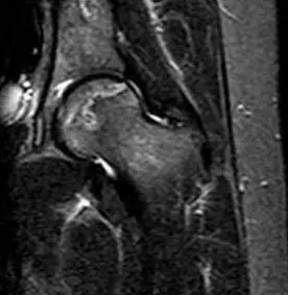

在股骨头坏死极早期,磁共振即可捕捉到特征性带状低信号、双线征等典型表现,比其他检查提前数月甚至一年发现问题,为保髋治疗赢得黄金时间。中晚期则能明确股骨头是否塌陷、关节受损程度,帮助医生制定科学治疗方案。

(T2加权像的双线征)